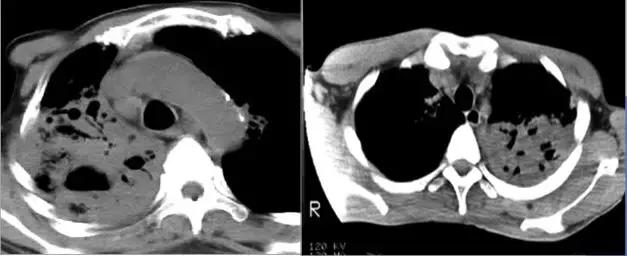

CT征象六:空洞与空腔

空洞(cavity)是肺内病变坏死液化,经引流支气管排除及气体进入而形成的透亮区。

空腔(aircontaining space)是肺内正常生理腔隙的病理性扩大。

空洞(cavity)分型 :

虫蚀样空洞(无壁空洞)

薄壁空洞(≤3mm)

厚壁空洞(>3mm)

疾病:大叶干酪性肺炎

疾病:继发型肺结核

结核球厚壁空洞

肺脓肿厚壁空洞

肺鳞癌厚壁空洞